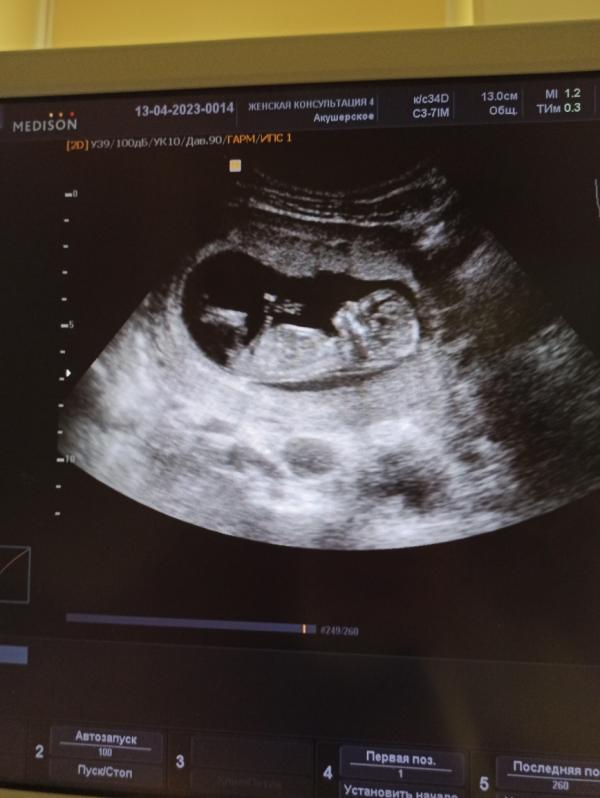

Прошла первый скрининг, с малышом всё хорошо, размер соответствует сроку!

Очень похоже на девочку💕

Кроха всего 6 см по ктр)

Ждём в 20 х числах октября😊